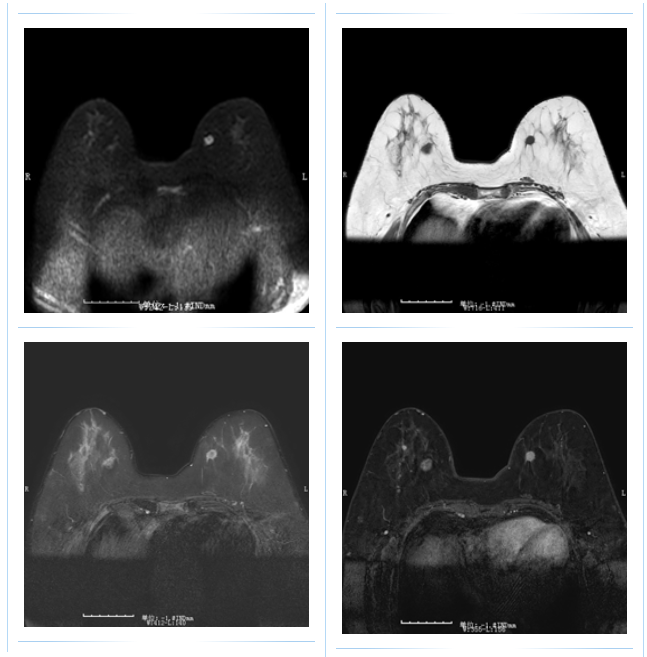

乳腺 MR 检查:乳腺健康的“精密利器”

乳腺 MR 检查,即乳腺磁共振成像,是一种无辐射的检查方法,对乳腺组织具有极高的分辨率,能够清晰展示乳腺的内部结构,为钼靶检查难以诊断的复杂病例提供重要补充。

软组织分辨率高:能够提供乳腺组织的三维图像,使乳腺结构的显示更加清晰,为医生提供更准确的诊断依据。

无辐射:特别适合年轻女性或需要频繁复查的患者,有效降低了辐射暴露的风险,让您安心检查。

多功能性:不仅可用于乳腺疾病筛查,还能在乳腺癌的分期、治疗效果评估等方面发挥重要作用,为您的乳腺健康提供全方位的保障。

当然,乳腺 MR 检查也存在收费较高、检查耗时较长的缺点,但在精准诊断方面,它无疑是值得信赖的选择。